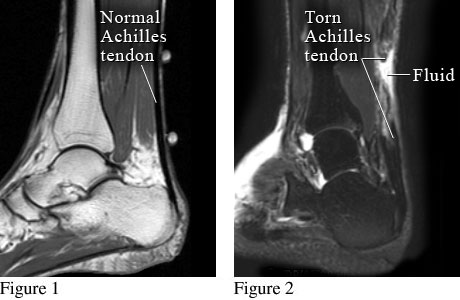

Normal Achilles tendon and torn Achilles tendon

Courtesy of Intermountain Medical Imaging, Boise, Idaho.

Figure 1 shows magnetic resonance imaging (MRI) of a normal heel and Achilles tendon. Figure 2 shows a torn Achilles tendon with fluid collected at the site of the tear.